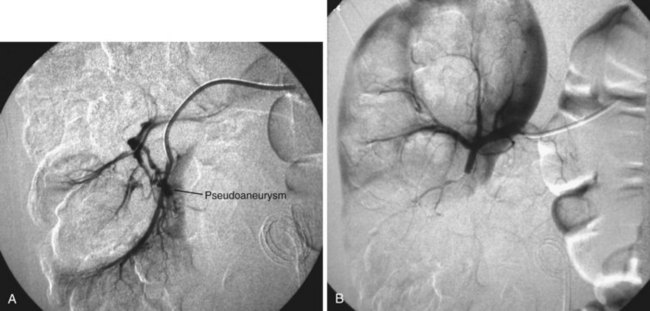

A ureteroscope passed retrograde can greatly facilitate percutaneous entry into the intrarenal collecting system (Grasso et al, 1995; Kidd and Conlin, 2003; Patel et al, 2008) by allowing the surgeon to observe and correct the percutaneous placement of a needle. A basket can then be passed through the ureteroscope to grasp the end of the percutaneous guidewire; pulling this out the urethra provides through-and-through access (Fig. 47–13). Even if the pathology being addressed is so large that direct visualization of the percutaneous needle is obscured (e.g., complete staghorn calculus), the ureteroscope can still be used to rapidly attain through-and-through access. Moreover, the ureteroscope may have better access to some sites in the kidney than the nephroscope and can be used to assist in the procedure (e.g., fragment or relocate stones, fulgurate small tumors).

Figure 47–13 Ureteroscope retrograde assistance. The needle can be directly visualized entering the calyx, and a wire can be grasped and pulled down the ureter and out the urethra.